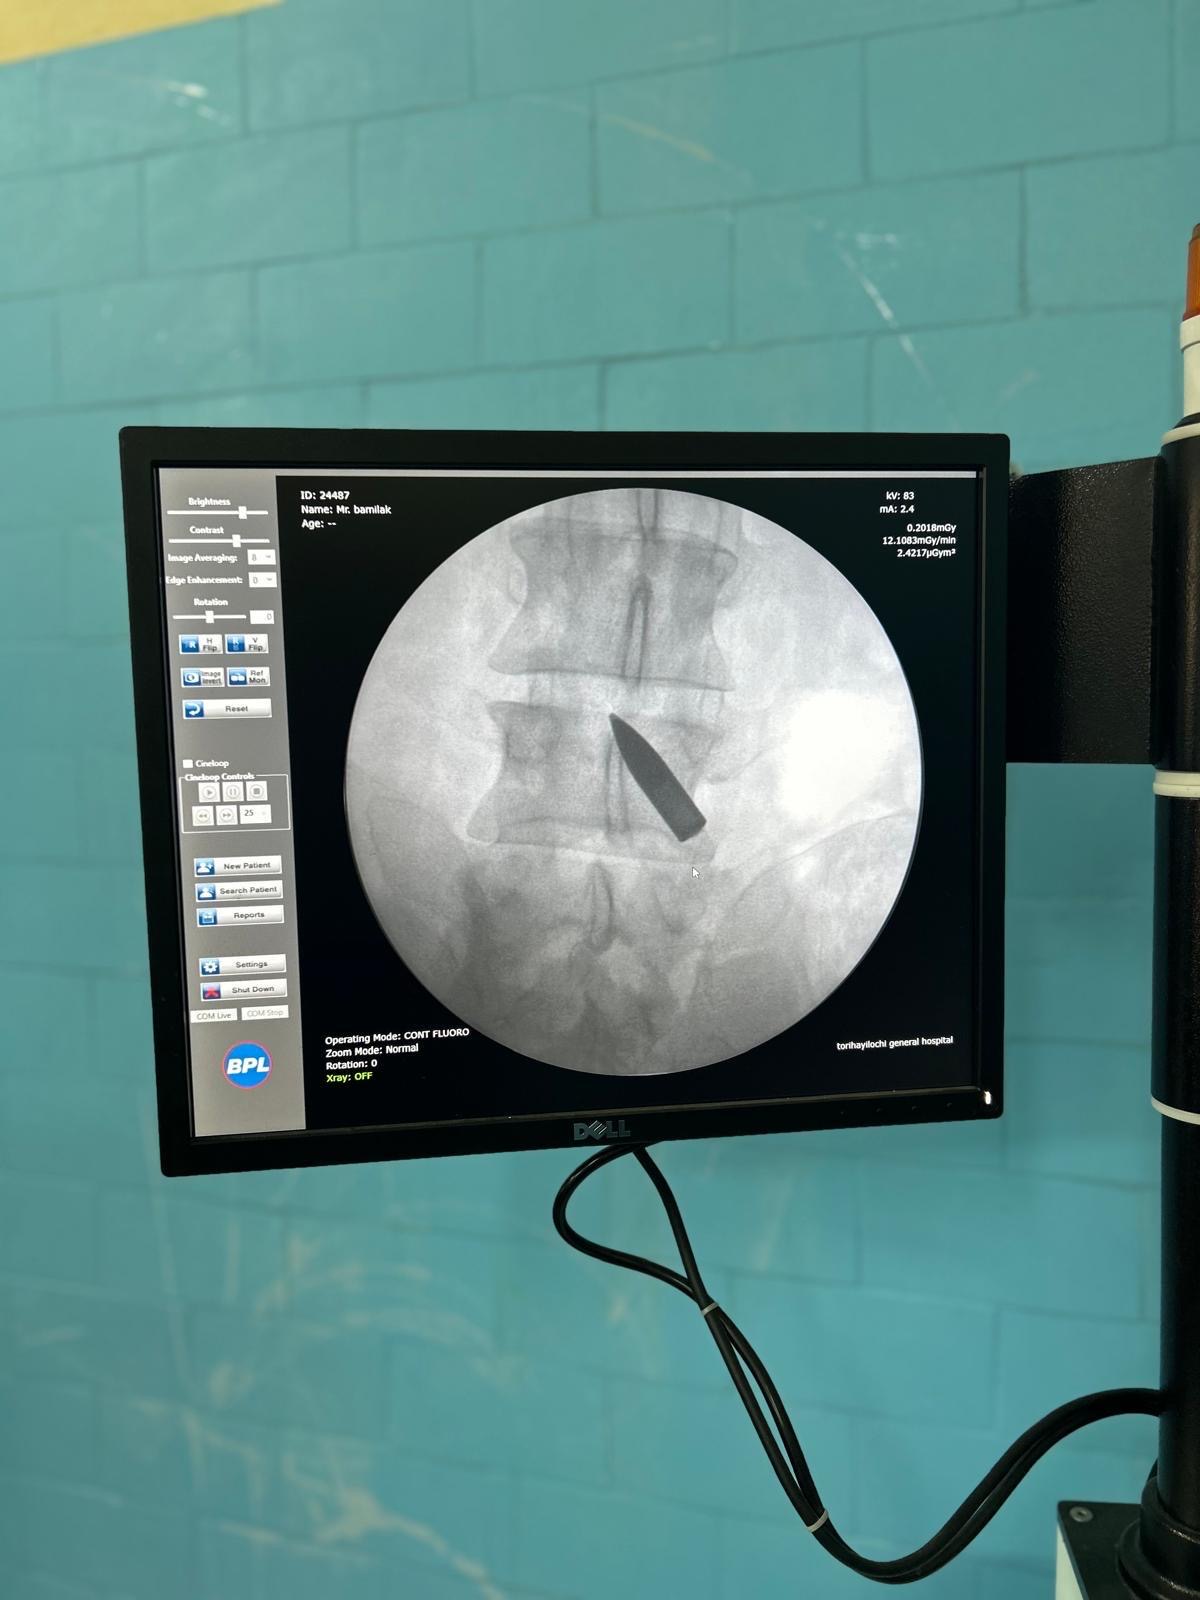

O warunkach tam panujących, najpoważniejszych zabiegach jakie przeprowadzali oraz o wspaniałych osobach organizujących pomoc powiedzieliśmy na 93,6 FM.